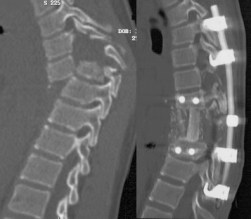

les fractures-dislocation de la région thoraco-

lombaire

on les rencontre à la suite d’AVP ou de défenestration.

la paraplégie peut être présente d’emblée ou survenir secondairement par déplacement d’une fracture instable

la réduction et la stabilisation peuvent nécessiter un abord antérieure et postérieur.